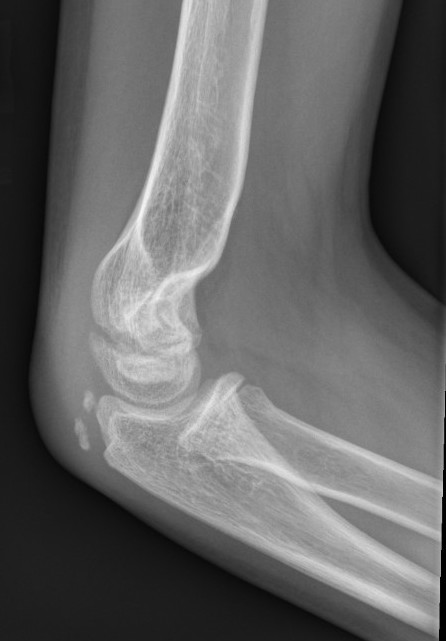

Lateral Xray

Position for good lateral

- thumb vertical

- hand above elbow

Anterior angulation

- shaft - condylar axis

- normally 40o

Lines

Anterior humeral line (AHL)

- should pass through middle of capitellum

Radio-capitellar line

- pass through capitellum

Teardrop

- shadow above the capitellum

- anterior dense line: posterior margin of the coronoid fossa

- posterior dense line: anterior margin of the olecranon fossa

- inferior portion: ossification center of the capitellum